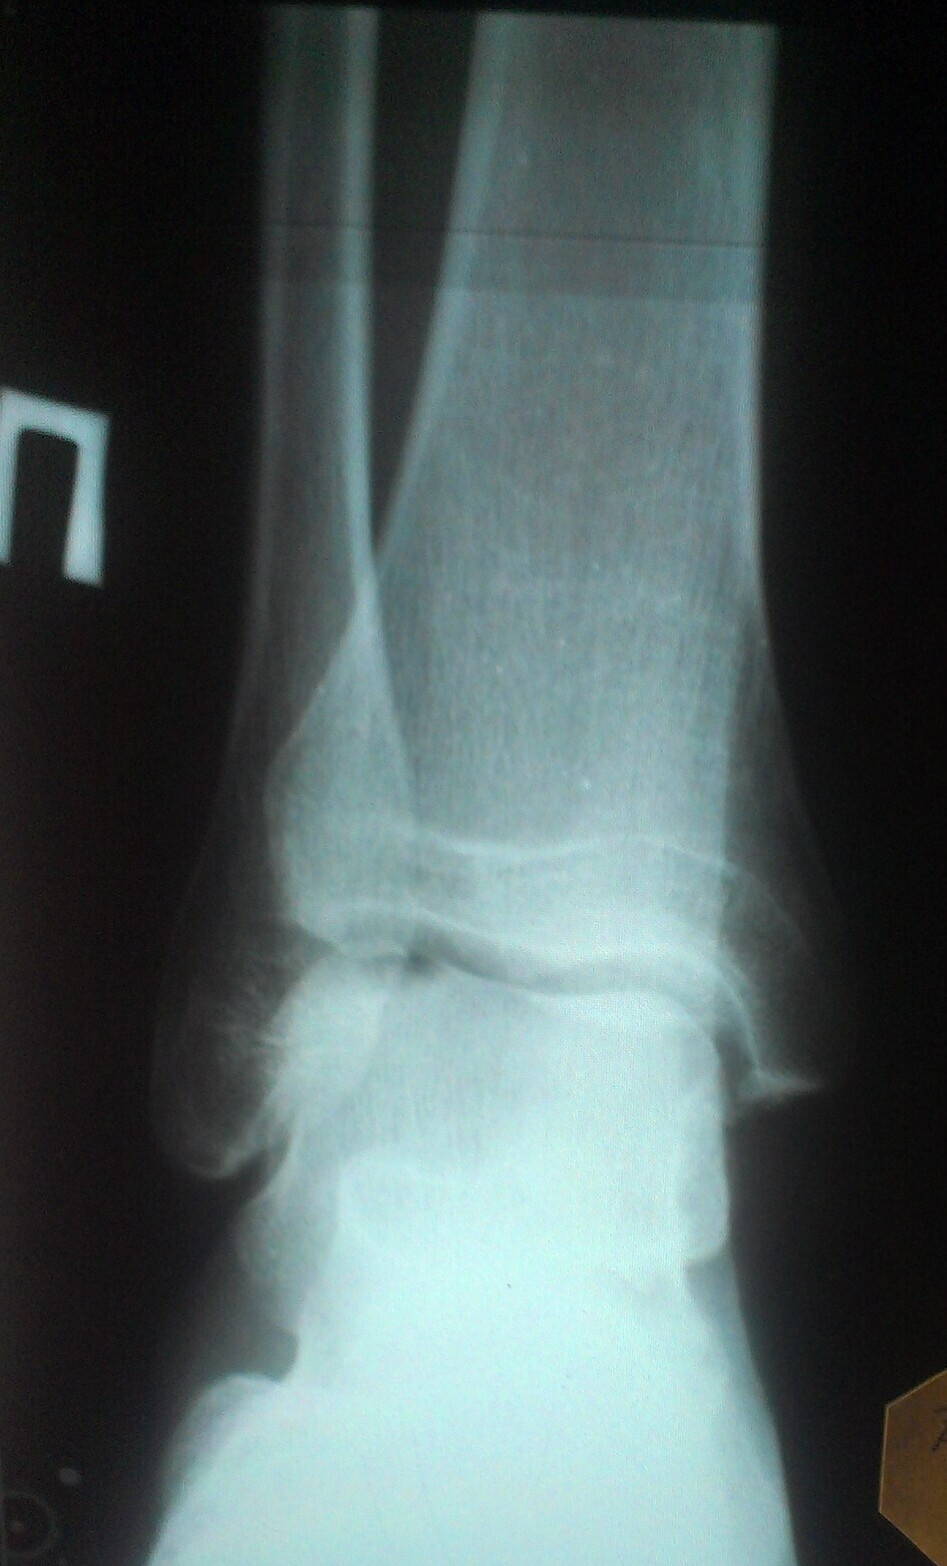

"История болезни"

01.02.12 (на тренировке)

Вернулся после перерыва в 2 месяца (сдавал сессию) на тренировки муай-тай. На тренировке упал и подвернул ногу. Заболела. Полежал. Встал, тренер сказал если щас же разбегаешься то пройдет быстро. Ну я продолжил треировку, хотя голеностоп такое ощущение что очень сильно налился жидкостью. Тренировку почти до конца закончил, но на следующий день все очень посинело и распухло и меня повезли на скорой в травматологию.

02.02.12 (4 травматалогия)

В 4й травматологии сделали рентген, сказали трещин пока не видно, но нужно будет еще позже проверить на повторном снимке. Перелома нет. Сказали повреждение связочного аппарата, повесили гипс на голень и стопу, гипс носил до 14ого, потом еще неделю дома носил повязки.

14.02.12 (студенческая)

В студенческой сделали повторный рентген, сказали трещин нет, на ногу внешне не смотрели. Сказали бинтовать эластичным бинтом и мазать долобене. Чуть чуть помазал, мотал бинтами долго.

7.06.12 (студенческая)

Снова в студенческую пошел так как не проходила нога. Сделали рентген, внешне ногу не смотрели. Сказали дисплазии нет, есть воспаление сустава, непонятно почему. Назначили компресы с Димексид+Гидрокартизон, мазь Дип-Хит и Фламидез таблетки 2шт/день в течении 10-12 дней.

Июль 2012 (17 детская)

В травматологии врач осмотрел ногу и снимки, сказал на первом снимке были трещины, а воспаление/отек сохраняется по сей день из-за того, что раньше положенного начались нагрузки на ногу, раньше чем нужно снят был гипс и пр. Прописал массировать ногу от голени до бедра, мази долобене+лиотон, 2 недели таблетки мовалис+лоратодин, эластичный бинт/повязку восьмерку. В итоге стало лучше, но не прошло.

Ноябрь 2012 (17 детская)

Все еще не проходит. Осмотрели ногу в той же травматологии. Сказали Артрон Комплекс пропить + мази + немного разрабатывать ногу.

5.02.13 (17 детская)

Осмотрели ногу, сделали рентген, было подозрение на кисту, которое не подтвердилось. Для уточнения пошел с рентгенами к професору, который сказал, что Болезнь Кенига.

Февраль 2013 (поликлиника на молодежной)

Решил заглянуть в местную поликлинику, врач посмотрел на снимки, ногу не смотрел, сказал артроз и направил в Ситенко, что бы там "тебе напишут направление на физиопроцедуры всякие".

Февраль 2013 (2 травматология)

Сделал КТ, пошел с рентгенами к хирургу, который сказал что: остеоартроз правого голеностопного сустава, кистозная форма. Выписал Аркоксия + Артрон Комплекс и предложил в случае если лекарства не помогут операцию по замыканию сустава. Общее состояние охарактеризовал как плохое. Я за тот день сжег больше нервов чем за всю жизнь до этого.

18.02.13 (институт протезирования)

Врач осмотрел ногу, сказал, что врожденное небольшое отклонение, которое без нагрузок осталось бы незамеченным, но при занятиях спортом дало о себе знать. Посоветовал купить ортопедические стельки и специальный бондаж на голеностоп. Еще советовал препарат "Структрум" и препарат для внурисуставных уколов "Останил". Сказал, что, возможно, был какой то надрыв хрящевой ткани сустава. Общее состояние охарактеризовал как безпроблемное и сказал, что при таких малых повреждениях даже артрон пить не обязательно.

19.02.13 (областная больница на универе)

Врач осмотрел КТ и рентгены, сказал болезнь Кенига в 3-4 стадии и сказал, что нужно делать операцию - артроскопию. Сказал после операции смогу плавать/велосипед/бег в кросовках с суспенаторами, но ударные единоборства, баскетбол, большой тенис и прочие ударные осевые нагрузки - нельзя. С операцией сказал не тянуть.

20.02.12 (ситенко)

Врач осмотрел ногу, рентгены и КТ. Сказал что есть небольшая дисплазия, что есть начальная стадия болезни кенинга, есть некоторое повреждение хряща, но сказал что операция не нужна. Сказал купить специальный бондаж на ногу (второй раз мне его советуют, ~$160, Malleo Train) и побегать/попрыгать в нем неделю, а потом прийти к нему на осмотр и он посмотрит что изменится за неделю под нагрузкой. Никаких таблеток сказал не нужно.

XnY6OQmJOwk.jpg

XnY6OQmJOwk.jpg [ 237.18 КБ | Просмотров: 2547 ]

КТ.jpg

КТ.jpg [ 483.5 КБ | Просмотров: 2547 ]